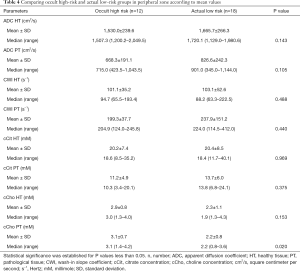

The MRI data classified 9 (34.6%) patients as T2 MRI and 17 (65.4%) patients as T3 MRI. Mean values, SDs, median ADC and CWI values, and citrate and choline concentrations for targeted zones of interest in healthy and pathological tissue are displayed in Table 1.

Topographic MRI data from the post-operative LR (n=8) and HR (n=18) patient groups showed a high proportion of T3 MRI findings (77.8% vs. 37.5%) in HR patients (Tables 1,2).

The mean abnormal ADC values were markedly lower in the HR group than in the LR group, although the difference was not statistically significant (P=0.06). However, cCho mean values were significantly higher among HR patients (3.6 vs. 2.2; P=0.001).

We observed that ADC and cCho values were within the same range as in the previous group, with choline levels significantly higher among HR patients (Table 3).

Analysis of the PZ

In the PZ, choline levels were consistently significantly higher in patients with occult HR, as well as in the pre-operative HR group compared to the pre-operative LR group (cCho, 3.1 vs. 2.2; P=0.020; and 4.1 vs. 2.7; P=0.013, respectively) (Tables 4,5).

Citrate values were always higher, regardless of the compared groups, although the difference was not statistically significant.

The steep decreasing ADC trend was confirmed among patients identified as pre-operative HR, as well as among occult HR patients. However, the difference was not statistically significant.

Regardless of the compared groups, CWI showed no significantly discriminating values between the risk groups, despite a slightly faster rise among HR patients (264.0 vs. 218.7 s−1).